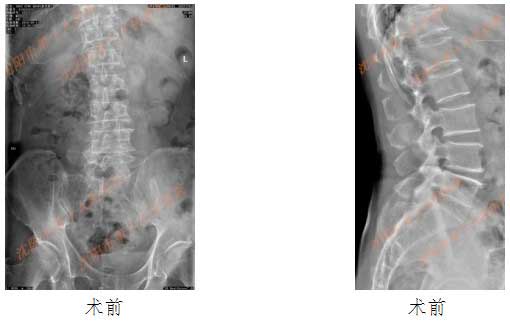

典型病例2: 女性患者,54岁,腰椎退变性侧突,不稳定。

患者在抬东西后出现腰痛,以胀痛为主,无下肢症状。理疗、按摩、针灸、火罐及汗蒸治疗约1个月,腰痛无缓解。到个体骨伤诊所行牵引、手法复位等理疗,腰痛无缓解,且出现双侧腹股沟区疼痛。

DR显示:腰椎前曲增大,向左侧弯曲,腰椎3-4椎间隙变窄。

行OLIF入路手术,术后患者腰痛及腹股沟放射痛症状解除,术后DR显示椎间高度恢复,畸形得到纠正。